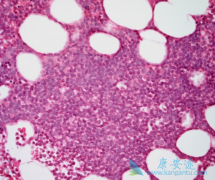

华氏巨球蛋白血症 (WM)的常见症状有乏力、虚弱、体重减轻、发作性出血及高粘滞综合症,最常出现在较为年长的成年患者的骨髓中,对淋巴结与脾脏也可能产生影响,罹患此种罕见病的患者,急需一款新的疗法来降低病情的风险。华氏巨球蛋白血症(WM)是一 ...